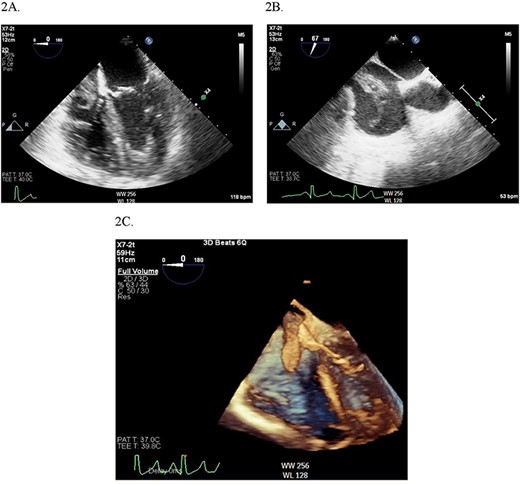

Continuous intraoperative transesophageal echocardiography (TEE) was performed. Postinduction TEE showed a large mobile mass of heterogeneous echogenicity in the RA abutting the tricuspid valve, mild tricuspid insufficiency, occlusive thrombus in the IVC and LV ejection fraction of 40% (Figs 2 and 3; Supplementary Materials S1 and S2). Given the location, size and mobility of the mass in the RA, the decision was made to remove it on CPB to minimize the risk of large embolus and significant blood loss. During the prebypass period, following laparotomy and drainage of abdominal ascites, the patient required significant colloid repletion with 5% albumin and blood products for hypotension, underfilled LV on TEE and low central venous pressure.

2D (A) and 3D (B) illustration of the IVC thrombus in long and short-axis views.